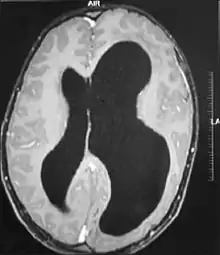

Гідроцефалія

Гідроцефалія — захворювання, що характеризується надлишковим накопиченням цереброспінальної рідини у шлуночковій системі головного мозку в результаті ускладнення її переміщення від місця секреції (шлуночки головного мозку) до місця абсорбції до кровоносної системи (субарахноїдальних цистерн (субарахноїдального простору)) — окклюзійна гідроцефалія, або в результаті порушення абсорбції — арезорбти́вна гідроцефалія.

Причинами гідроцефалії, в свою чергу, можуть бути:

- мальформація Арнольда — Кіарі;

- акведуктальний стеноз;

- Х-зчеплена гідроцефалія зі стенозом водопроводу;

- синдром Денді — Уокера;

- аневризма вени Галена або мальформація;

- голопрозенцефалія;

- розширений субарахноїдальний простір(часто внаслідок крововиливу);

- внутрішньошлуночковий крововилив;

- саркоїдоз;

- менінгіт чи менінгоенцифаліт.